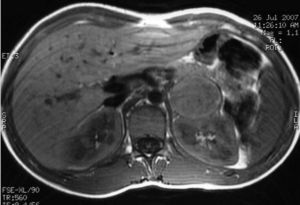

Case 2: A female patient diagnosed with NF-1 at nine years of age after the diagnosis of her mother (case 1). At 15 years of age she reported episodes of headache and palpitations. Physical examination found more than six cafe-au-lait spots and BP values of 154–83mmHg. Laboratory tests revealed basal blood glucose of 128mg/dL with no other changes, and a CT scan of the head and cardiological evaluation were normal. Urinary catecholamine and metanephrine tests were performed, with the following results: epinephrine, 150mcg/24h (NR: 0.5–20mcg/24h); norepinephrine, 713mcg/24h (NR: 14–80mcg/24h); metanephrine, 1757mcg/24h (NR: 86–320mcg/24h); and normetanephrine, 3967mcg/24h (NR: 129–400mcg/24h). MRI showed a nodule in the left adrenal gland, 4cm×4cm×3.8cm in size, hyperintense in T2, heterogeneous, and with necrotic areas (Fig. 2). MIBG scintigraphy showed left adrenal hyperfixation. Laparoscopic surgery was performed after treatment with phenoxibenzamine 20mg/12h, and a pathological examination confirmed the diagnosis of pheochromocytoma.